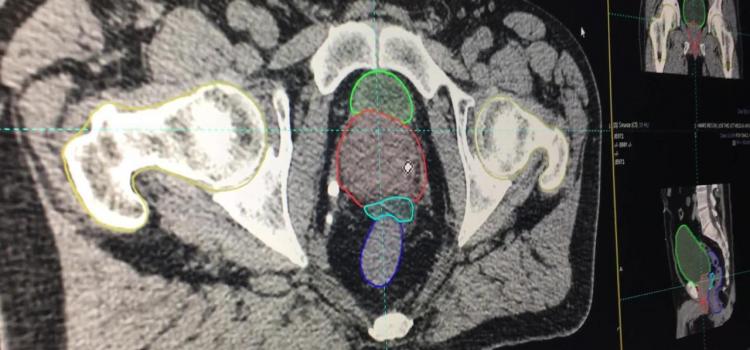

CT Virtual Simulation

This is an example of the Mirada DLCExpert deep learning software that automatically identifies organs, segments and ...